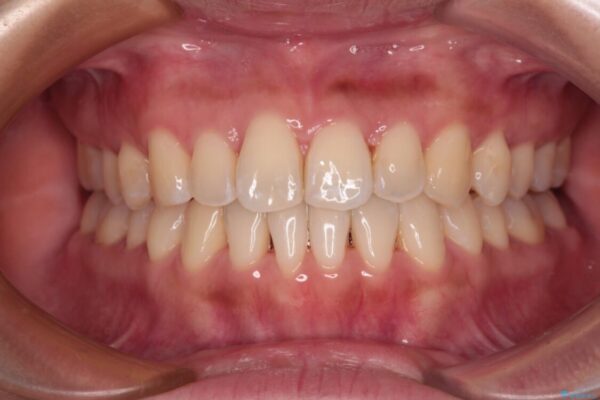

治療後

• 【モニター】前歯のデコボコをインビザラインで改善 治療後画像